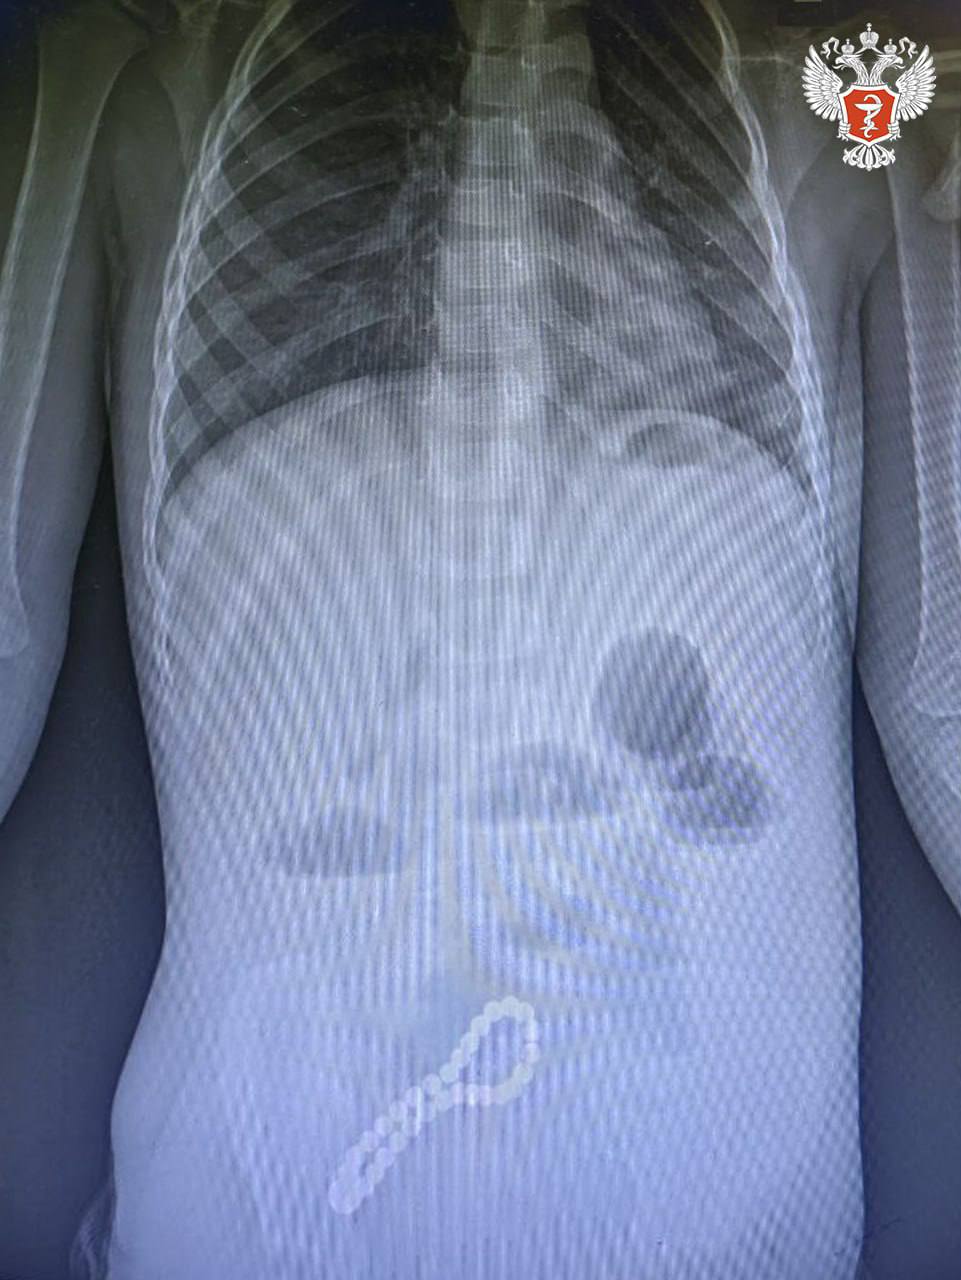

Трёхлетний мальчик поступил в клиническую больницу после того, как родители заметили ухудшение его самочувствия. Хирурги выявили нарушение работы кишечника, а рентгенография показала наличие инородного тела.

"[Врачи] провели минилапаротомию и увидели, что магнитами, которые притянулись друг к другу, соединены петли кишки в ее стенке отверстия. В ходе операции удалили все 30 магнитных бусин: 29 маленьких и одну большую. Сейчас ребенок поправился", — сообщили в Минздраве РФ.